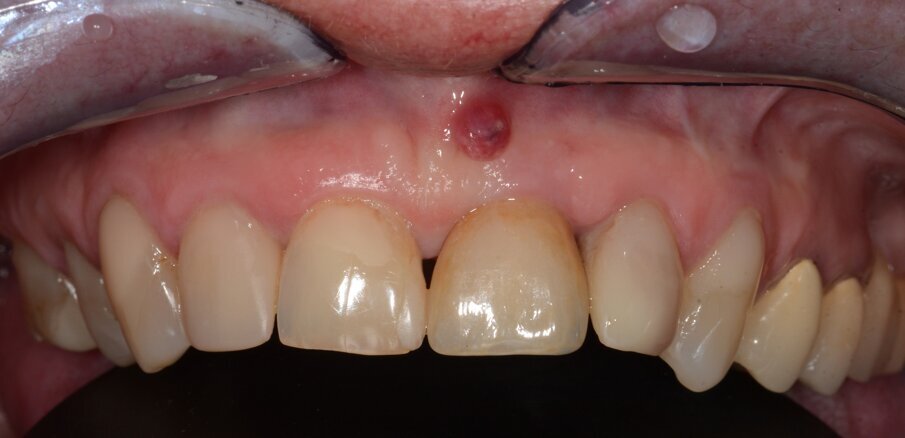

The implant apicectomy in Case 3 shows that one year after the immediate implantation with immediate loading there was inflammation around the implant apex. The rest was properly integrated (Figs. 13–20).

Fig. 13: Initial situation. Visible fistula one year after loading.